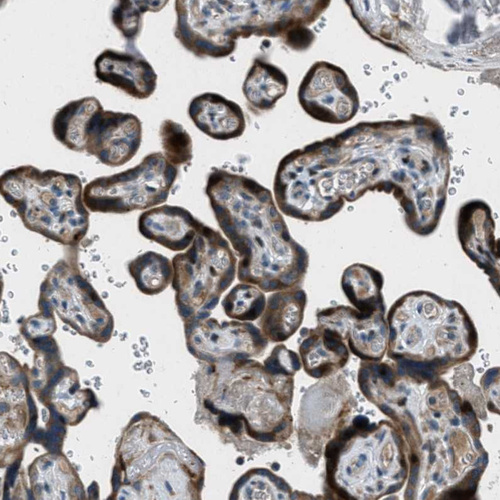

Immunohistochemical staining of human tonsil shows strong cytoplasmic positivity in germinal center cells.